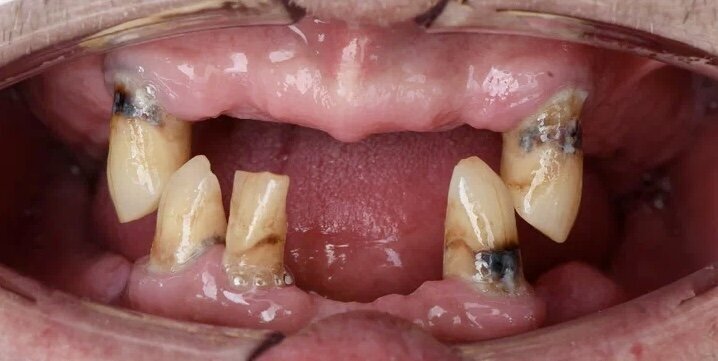

У пациента остались только несколько зубов на обеих челюстях, на которые невозможно установить несъемные конструкции. Ситуация до:

на верхней челюсти осталось 2 клыка, на нижней 2 клыка и 1 резец.

У пациента западает верхняя губа из-за отсутствия зубов, а следовательно нет поддержки мягких тканей, во фронтальном отделе и также нижняя челюсть выдвинута вперёд, за счёт отсутствия зубов в жевательном отделе. То есть прикус не фиксирован.

В полости рта выглядело примерно так: